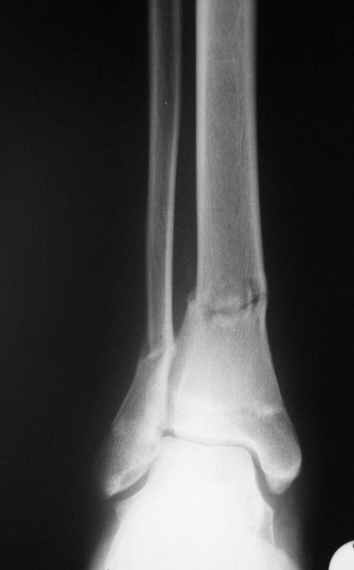

Уважаемый Виталий Евгеньевич,

Помятуя наш недавний разговор о фиксации м.б. кост, высылаю послеоперационные картинки..

Напомню- разбирали случай 17 летнего молодого человека перелом дист тиб.фиб. хирургия после 3 недель с момента травмы( безуспешные попытки закрытой репозиции) Раны заживают первичным натяжением, занимается физиотерапией, пока никаких проблем не наблюдается

Как ты тут оцениваешь восстановление оси большеберцовой кости?

Является ли рутинной практикой у вас использовать снимок противоположной конечности как шаблон для измерения осевых отклонений?

Согласный я с тобой:-)) есть остаточная вальгусная деформация (по снимку видно перекрывание дист. фрагментом б.б по латеральной поверхности проксимальноо фагмента на 2-3 мм и наружная лодыжка репонирована с укорочением, судя по прямой проекции. Необходимость использования интраоперационно дистрактора была бы оправдана (вручную было непросто *вытянуть* дистальный отломок.)

На мой взгляд, Ваша демонстрация неожиданно добавила перцу. Если память мне не изменяет, я говорил об отсутствии показаний к остеосинтезу малоберцовой.

Сейчас можно заикнуться о вредности этой манипуляции с точки зрения риска фиксации в неправильном положении, как это получилось у Вашего пациента. Сначала фиксировали большеберцовую, и надо было на этом остановиться, ин май хамбл опиньон. Потом при закручивании винтов на мощнейшей второй пластине сустав увело на вальгус. С учетом того, что пацану всего 17, я бы удалил пластину с малоберцовой и попытался тем или иным способом устранить смещение, пока не срослось.